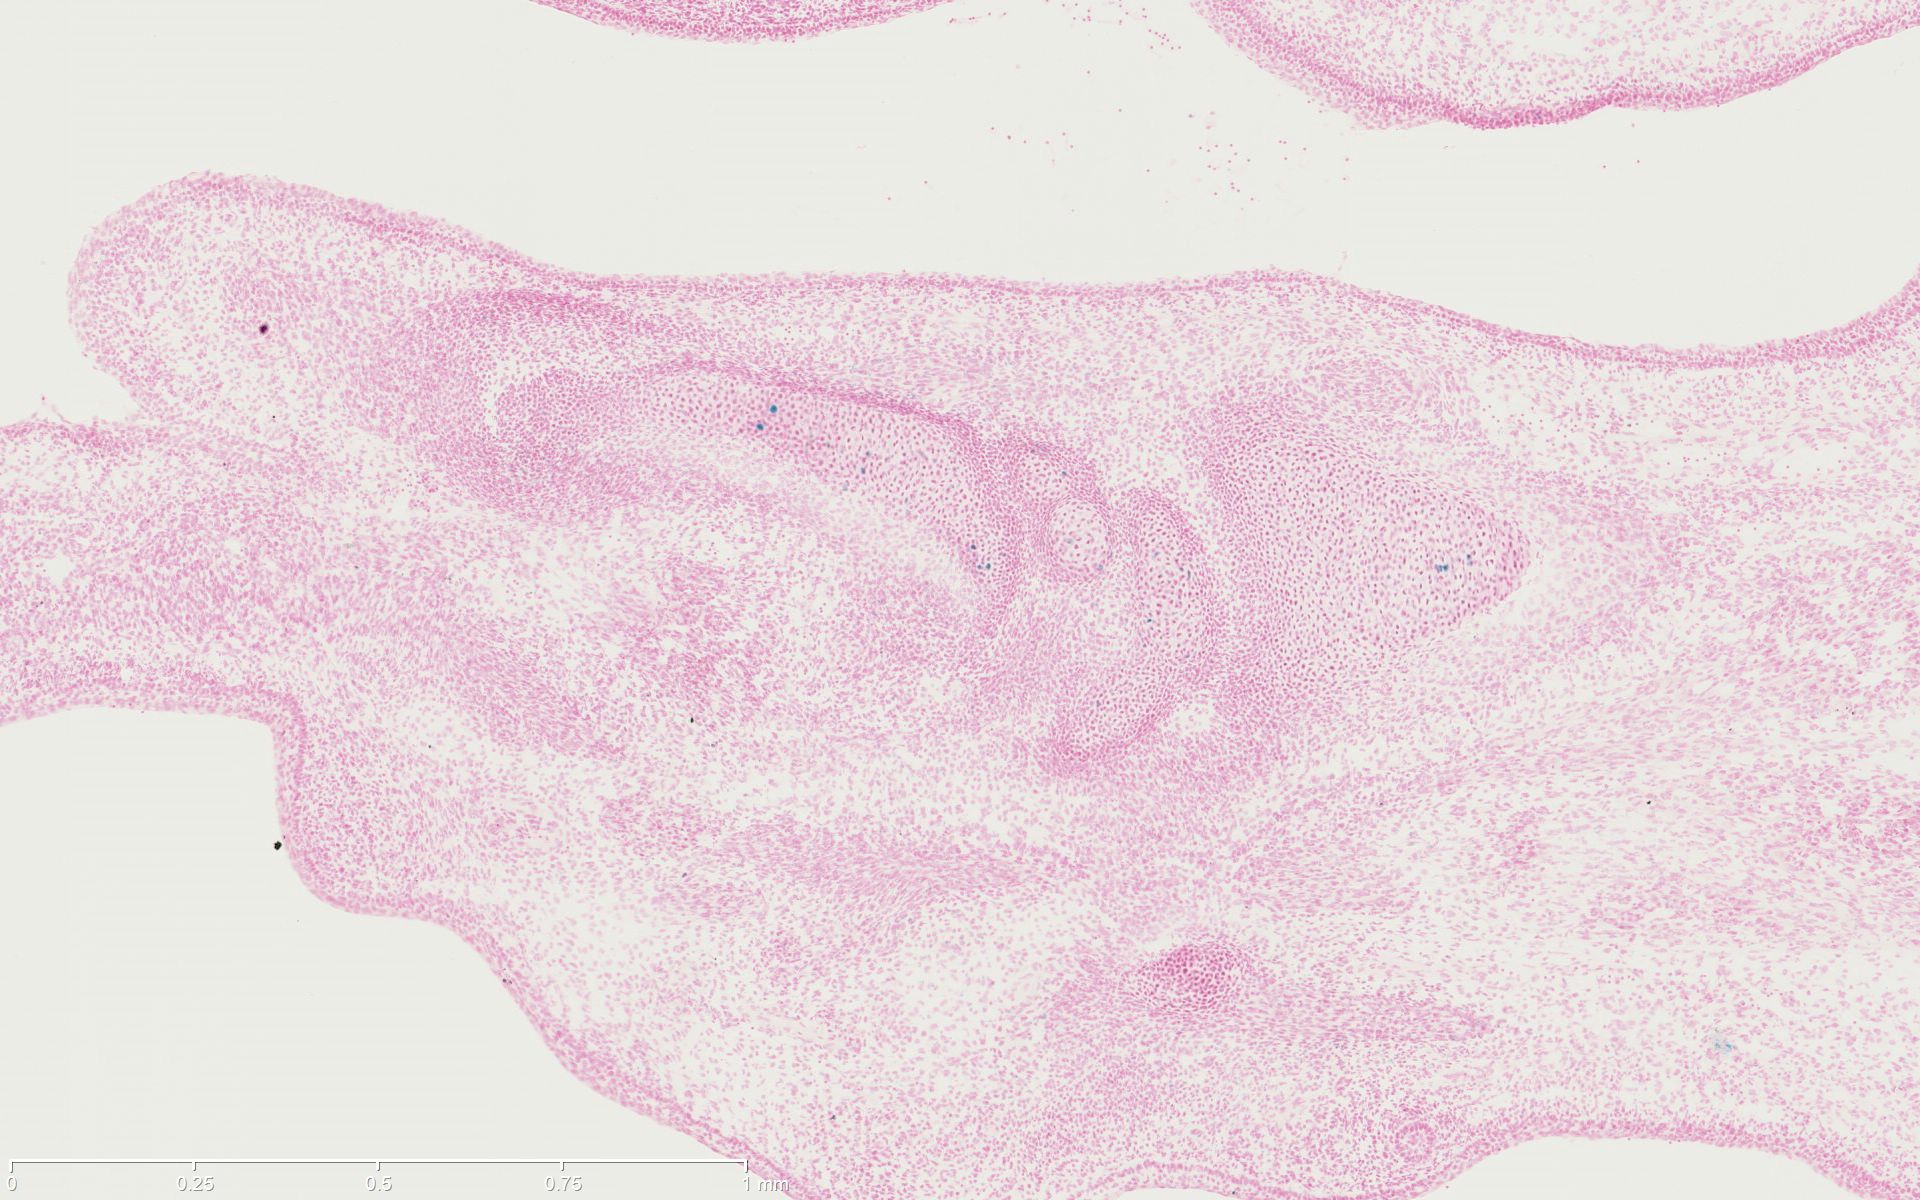

The transgene consists of a tamoxifen-inducible cre recombinase driven by the 2.3-kb mouse Col1a1, collagen, type I, alpha 1, promoter. The transgene insert contains a fusion product involving cre recombinase and a mutant form of the mouse estrogen receptor ligand binding domain. The mutant mouse estrogen receptor does not bind natural ligand at physiological concentrations but will bind the synthetic ligand, 4-hydroxytamoxifen. Restricted to the cytoplasm, the cre/Esr1 protein can only gain access to the nuclear compartment after exposure to tamoxifen. Inducible cre recombinase activity is detected in the osteoblasts of the long bones of the limbs and in the ribs, vertebrae and calvaria in 18.5 embryonic day aged and 18 day old mice. Inducible cre recombinase activity was not detected in chondrocytes.

Images

Drag images to compare to others or to data in the table below. Drag corners to resize images for more detail.

Recombinase Activity